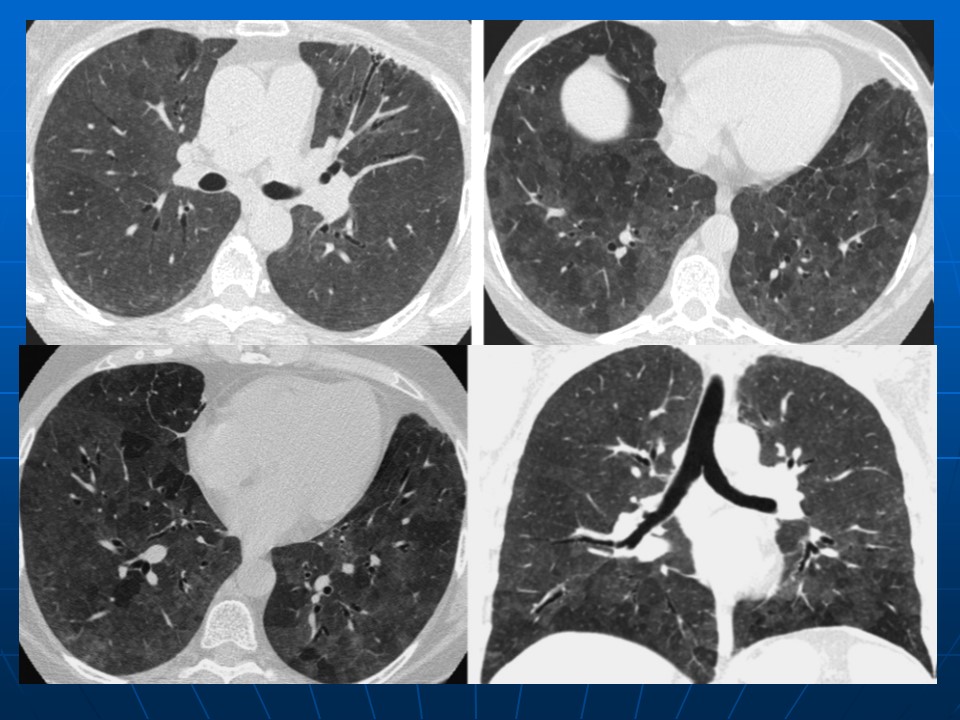

下一篇:【病例】肺动脉静脉畸形1例CT